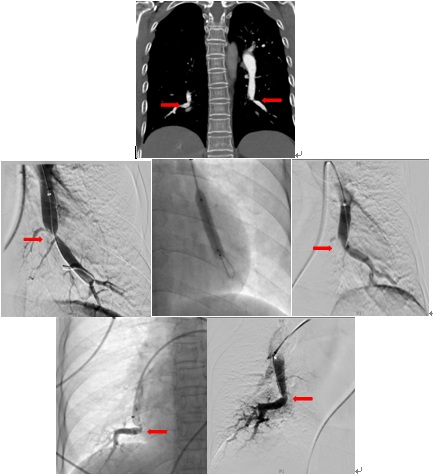

术前双侧肺动脉主干内血栓,术中溶栓后改善,术后复查主干血栓消失

北京清华长庚医院血管外科团队在吴巍巍主任的带领下联合麻醉科心内科呼吸科重症医学科等兄弟科室充分评估患者病情明确患者手术指征制定详细的围手术期治疗预案,与患者及家属充分沟通手术的必要性及相关风险后决定采用肺动脉球囊扩张成形术治疗。这是血管外科在静脉血栓栓塞性疾病治疗中的又一次大胆的尝试,无论是医生或是患者均承担了相当大的风险及压力。219日在麻醉科的严密监测下吴巍巍主任、赵俊来医通过右侧股静脉入路选择进入患者左肺动脉基底段狭窄部位,完成肺动脉球囊成形术,球囊扩张后肺动脉形态改善患者术后在监护病房观察一天后顺利返回普通病房,患者恢复顺利。于225再次行右侧肺动脉基底段球囊扩张。患者术后6分钟步行距离明显提高,术后2天即可行走450m,肺动脉力由术前82mmHg降至68mmHg患者顺利出院,由于双侧肺动脉病变广泛,此后还将密切随诊,择期再次行其余部位的肺动脉腔内治疗。